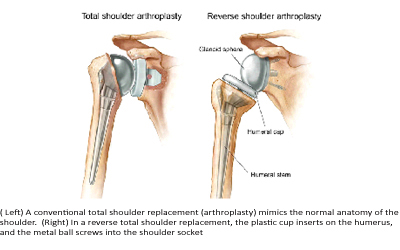

Total shoulder arthroplasty. Both the head of the humerus and the glenoid are replaced. A plastic “cup” is fitted into the glenoid, and a metal “ball” is attached to the top of the humerus.

Reverse total shoulder arthroplasty. In a reverse total shoulder replacement, the socket and metal ball are opposite a conventional total shoulder arthroplasty. The metal ball is fixed to the glenoid and the plastic cup is fixed to the upper end of the humerus. A reverse total shoulder replacement works better for people with cuff tear arthropathy because it relies on different muscles — not the rotator cuff — to move the arm.